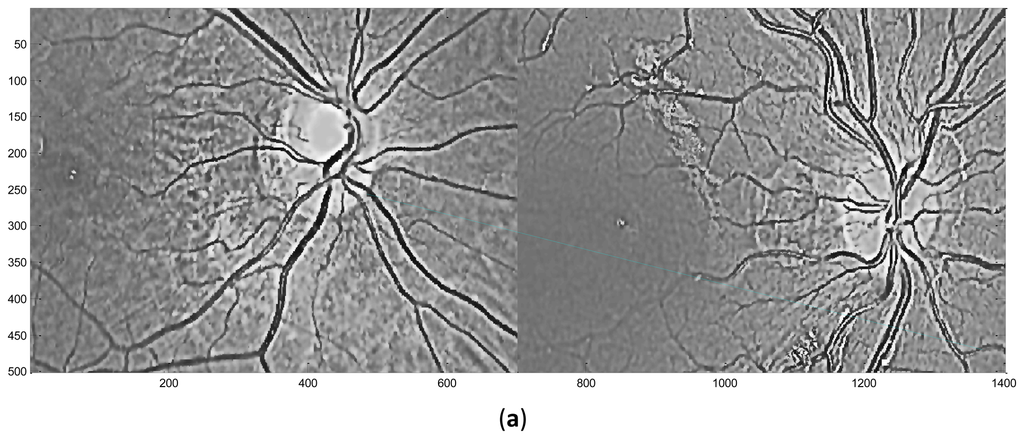

Here, Zr(x,y) represents the coefficient matrix of the real part of CGF and Zi(x,y) stands for the imaginary part. This operation means the retina images is convolved by the new template which is sum of coefficient of both the real and imaginary part of the original CGF, as can be seen in Figure 4. In this paper, we set F = 2.1, σ = 3.7 for the template. The result P after convolution is shown in Figure 5b, It should be noted that for viewing convenience, P is normalized to values from 0 to 255. From the image shown in Figure 5b, we can see that P is a bias-like image generated from the original retinal image.

The final retinal image is defined as:

Here, R is the final retinal image resulted from the proposed ICGF. This operation is simulated as removing the additive bias from the original retinal image. R′ is the temporal variable, its values range from [−255, 255] and is normalized to [0, 255] for further processing. R is shown in Figure 5c, we can see that the image processed by the ICGF has a stronger gray level contrast than the original retinal image, and has a substantially uniform grayscale distribution.